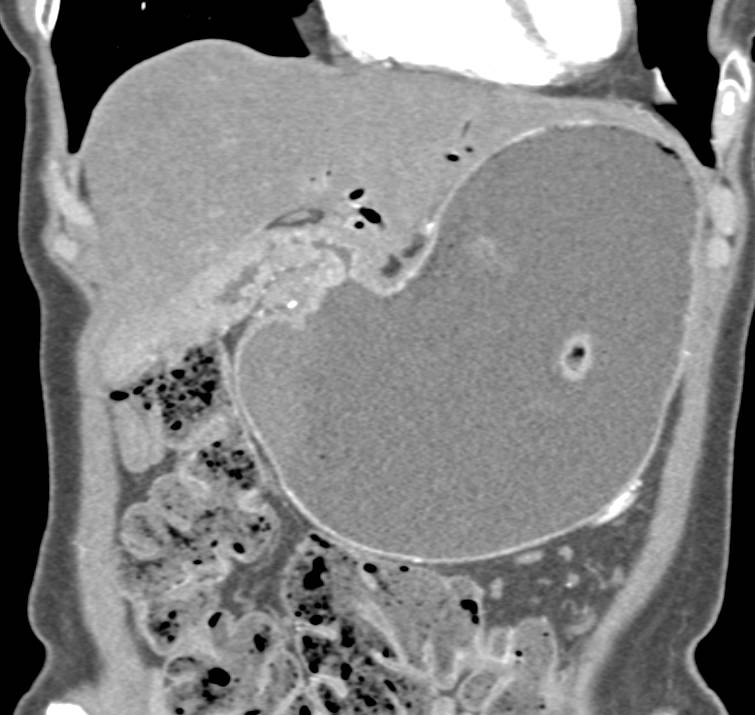

Recurrent Gastric Cancer